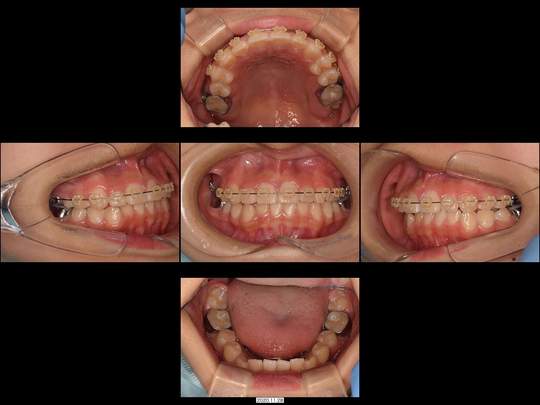

矯正前

画像をクリックで拡大

矯正後

治療の説明

「前歯の重なりが気になるので、部分矯正で改善したい」というケースです。またカウンセリング時に細かいお話を伺ったところ「口元の印象もスッキリさせたい」とのこと。

部分矯正では無理な治療計画となる可能性が高かったため、抜歯してスペースを確保し、表側ワイヤー矯正装置を用いて全体矯正にて対応しました。

治療の期間・回数

20か月、24回

​費用

1,007,600円